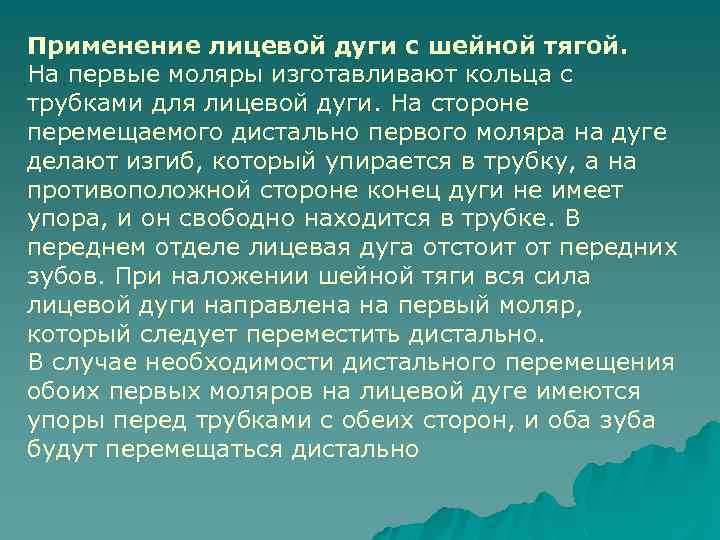

Применение лицевой дуги с шейной тягой. На первые моляры изготавливают кольца с трубками для лицевой дуги. На стороне перемещаемого дистально первого моляра на дуге делают изгиб, который упирается в трубку, а на противоположной стороне конец дуги не имеет упора, и он свободно находится в трубке. В переднем отделе лицевая дуга отстоит от передних зубов. При наложении шейной тяги вся сила лицeвoй дуги направлена на первый моляр, который следует переместить дистально. В случае необходимости дистального перемещения обоих первых моляров на лицевой дуге имеются упоры перед трубками с обеих сторон, и оба зуба будут перемещаться дистально